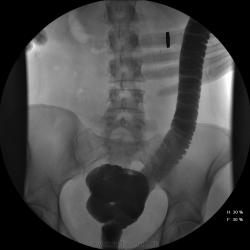

Девушка, 27 лет, жалуется на периодические боли в правой подвздошной области, области паха справа. Во время этого идет нарушение стула - то слабит, то несколько дней не может ходить в туалет, вздутие кишечника. Жалобы несколько лет . Обследованна кем только можно. Хирург посоветовал ирригоскопию. Работа достаточно нервная. До первого случая данных проблем , за неделю, проходила сан лечение в пансионате ( для поднятия общего иммунитета - так говорит), был курс клизм с травами - сама думает, что это не связанно.

Цепочка тенюшек - это наша "гордость)" следы от контраста после гистеросальпингоскопии. чтоб вымыть ,надо разбирать стол , а это только с представителем сименса. вот так.) а правые отделы толстой кишки на расширены? я кроме лополнительной петли сигмы сам ничего не вижу. несколько настораживает некоторое расширение правых отделов кишки- может за счет запоров, которые случаются у девушки? не хочется что то пропустить.

Коллеги, значит пишу долихосигма и все?

Считаю, данных за долихосигму нет.

Признак долихосигмы - это наличие т.н. симптома "трехстволки", есть это - есть и долихосигма. В данном случае такой вариант имеет место быть.

может и правда гаустрация левых оделов толстой кишки сглажена? интересно, а выраженность гаустрации зависитиот наследственных особенностей - у кого то лучше, у кого то хуже выражена? или все же сглаженность - признак патологии?

Явная сглаженость никак нормой быть не может...в том числе и слева...а уж если мелкая зубчастось, пусть и преходящая...а если и спастические скоращения на большом протящении...а если и неровность и несимметричность гаустр...а если и боль при рентгенопальпации...а если и изменения структуры рельефа...вот тогда и о КОЛИТЕ поговорить можно...